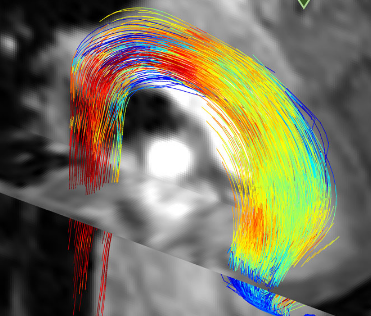

特别地,4D流量MRI测量能够量化血流的动态变化。这样的动态图像非常有用,特别是在检测心血管疾病时。

研究人员能够证明这种方法可以像他们最近发表的论文中所述的那样工作。他们使用对健康测试对象进行的11次MRI扫描对软件进行了培训。该数据足以在短短21秒内在普通计算机上准确再现患者主动脉中的病理性血流。因此,该方法比传统方法快许多倍,并且,最重要的是,可以提供更好的结果。